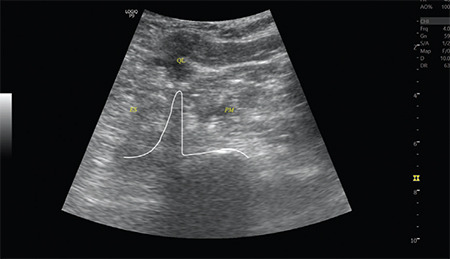

Facioscapulohumeral muscular dystrophy (FSHD) is a muscular dystrophy that can affect individuals of all age groups. Its prevalence is reported to be 0.4-1 in 10,000 people. Because of the low occurrence of FSHD, anaesthetic management is primarily based on expert opinions, case reviews, or brief series. Here, we present the case of a 72-year-old woman with FSHD who underwent hip fracture (HF) surgery. To prevent respiratory compromise due to FSHD, we opted for lumbar-sacral plexus block. To the best of our knowledge, there is no information in the literature regarding the use of combined lumbar-sacral plexus block in patients with FSHD undergoing HF surgery.